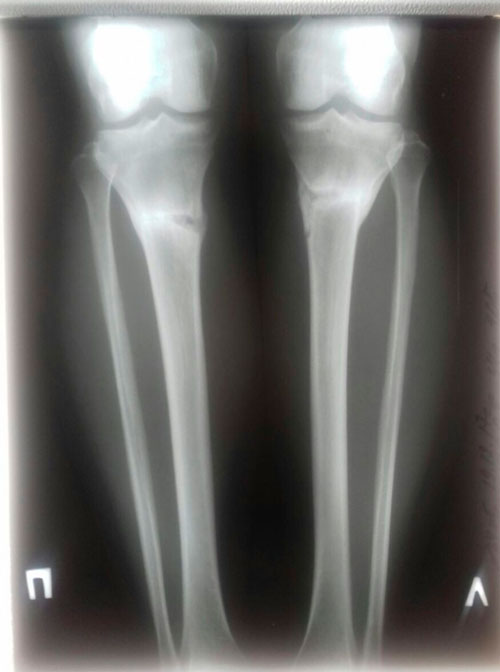

рентген и фото ножек, через 2 месяца с момента снятия аппаратов.

Сращение отличное, разрешено обувать каблучки, привыкайте к красивому!

Физические нагрузки разрешены (спорт) постепенно, по нарастающей.